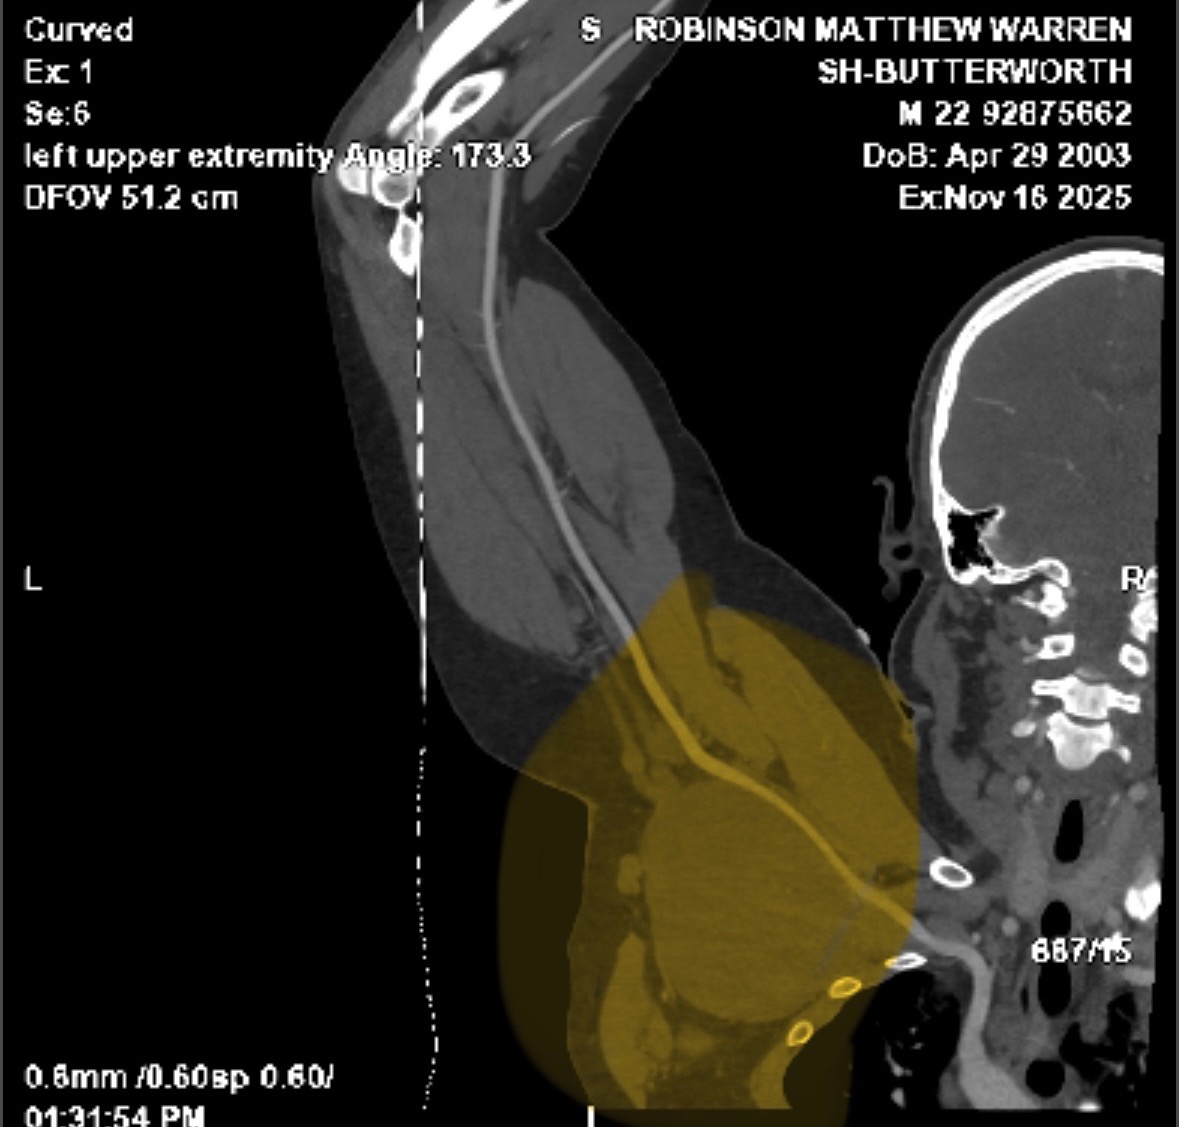

My last surgery was early last year, and recovery has gone well, but a relatively new problem has come up. In the last year or two, we discovered that a tumor in my left arm has been growing pretty aggressively and is starting to concern doctors enough that they are planning surgery. Hopefully, by the end of January or early February, this time surgery is slightly more risky than my previous ones due to the number of nerves that are running through the tumor. They are predicting about a 10% chance of losing feeling in parts of my arm and a slight chance I lose the ability to use my arm at all.